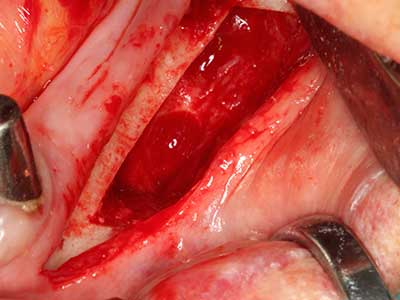

Fig. 27: paziente di 21 anni dopo osteotomia di conversione con retrognazia persistente e disgnazia di seconda classe.

Fig. 28: durante la rimozione del metallo, le regioni basali del mento vengono separate con Piezomed, mantenendo l'apporto sanguigno alla lingua.

Fig. 29: spostamento in avanti del mento di 5 mm e fissaggio con due piastre di osteosintesi (KLS Martin). È possibile individuare i due nervi mentonieri nella regione marginale.

Fig. 30: il miglioramento estetico del contorno del mento dopo l'operazione è chiaramente visibile.